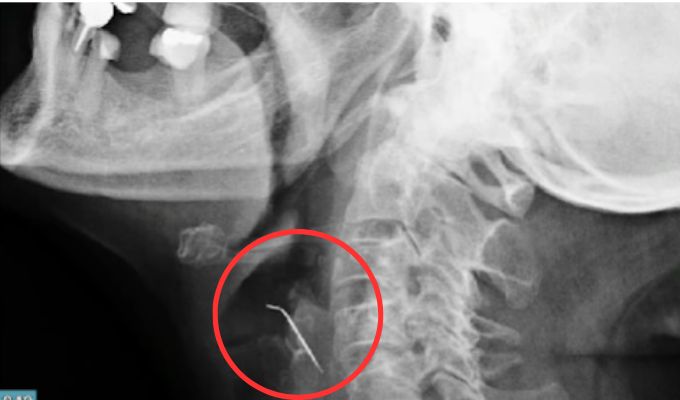

¡Sorprendente! Personal médico de EsSalud le salva la vida a una adulta mayor que tenía más de 40 días con un clavo atravesado en la arteria carótida. Este objeto de metal se encontraba incrustado en un chicharrón que la mujer se comió en el cumpleaños de su hija.

¡Se salvó de milagro! Este objeto metálico, que se encontraba oxidado, estuvo 43 días en el cuerpo de la paciente.